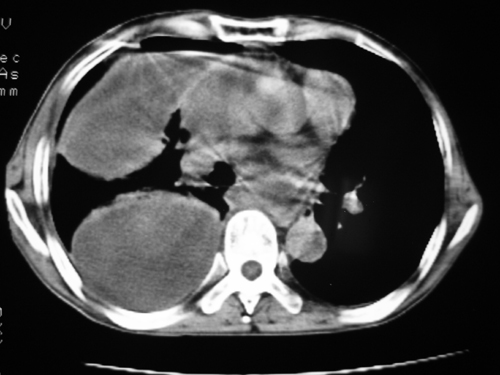

以下是引用yangyudong333在2008-4-29 5:46:00的发言:[br]1左上叶结节呈分叶状,边缘毛刺,考虑肺癌并纵隔淋巴结转移可能性大,结核待排,[br] [br]2右侧多发包裹性胸腔积液